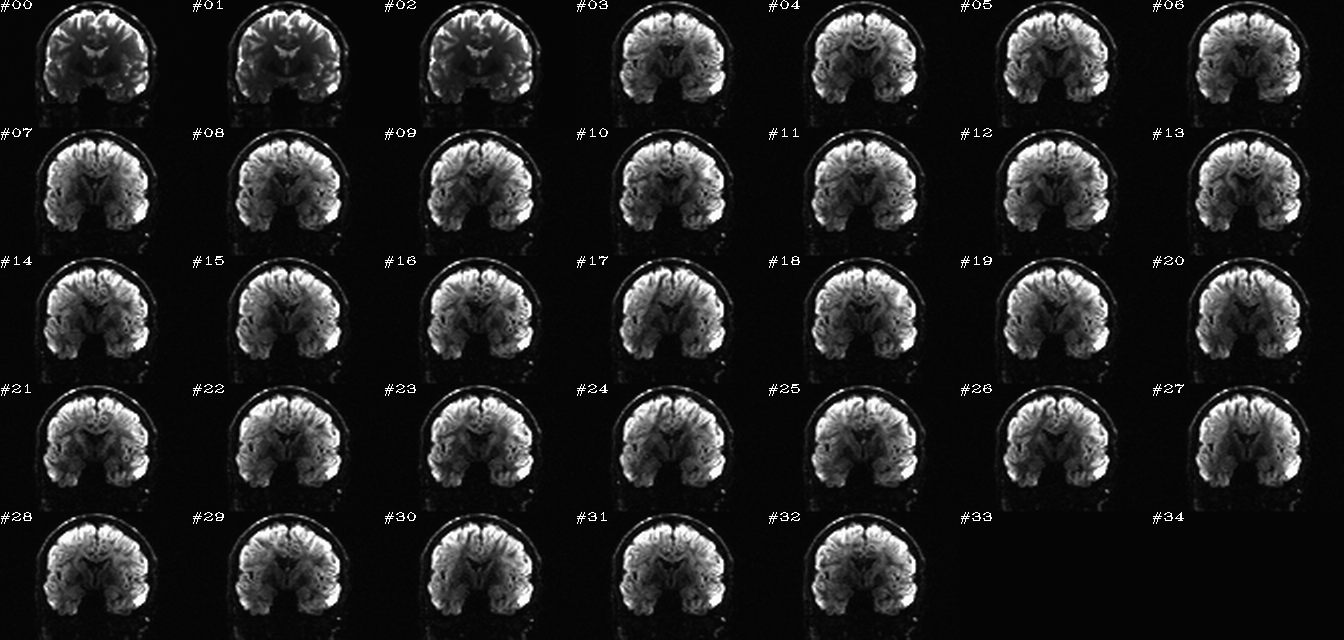

For 4D data, the montage typically shows a single slice across all time points (which, for DWI, might just represent different DW volumes). The N images are arranged in something close to a golden ratio array, padded at the end as necessary to have a solid grid of images. Additionally, a GIF or MPG movie may be created. Images may have a single scaling (grayscale: black=2% and white=98% brightness) across the whole volume (“onescl”) or separate scalings (again, 2-98%) for each volume (“sepscl”), each highlighting useful features for comparisons.

These images represent a benefit of batch processing: one can systematize the visual checks of processed data. That is, we can create very similar, comparable views across the group of data being processed, and then one can look through all these images quickly in succession to check for similarity or subtle patterns of difference. I find these sets of images very helpful for the process of understanding my data, checking the homogeneity of processing across a group, and seeing quickly any subjects that need to be reprocessed. These are also very useful sitting down with someone else (supervisor, student, colleague, etc.) and showing a lot of processed data quickly.